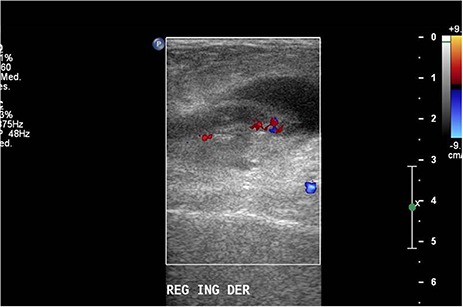

Ultrasound was performed with a Philips iU22 ultrasound using a 9 MHz linear transducer. A well-defined cystic mass was observed over the area. Right in the middle, a tubular image that terminated in a blind-ended tip in the longitudinal plane (Fig. 1A) and a target appearance on the cross-sectional plane (Fig. 1B) consistent with the appendix were demonstrated. The appendix measured 0.63 and 0.72 mm, discreetly above normal range, and it showed hypoechoic thickening of the mucosal layer. Color Doppler flow of the tip (Fig. 2) and adjacent soft tissue showed inflammatory changes. The patient presented pain on compression with the transducer. The surrounding fat tissue presented increased echogenicity suggesting inflammatory tissue. The preoperative surgical diagnosis was a strangulated inguinofemoral hernia. However, the findings were reported as acute appendicitis within an inguinal hernia sac. Inguinal hernioplasty with inguinal exploration and repair of an inguinofemoral hernia and resection of intestinal contents were performed (Fig. 3).

Figure 2.

Doppler ultrasound with increased flow on the tip of the appendix.